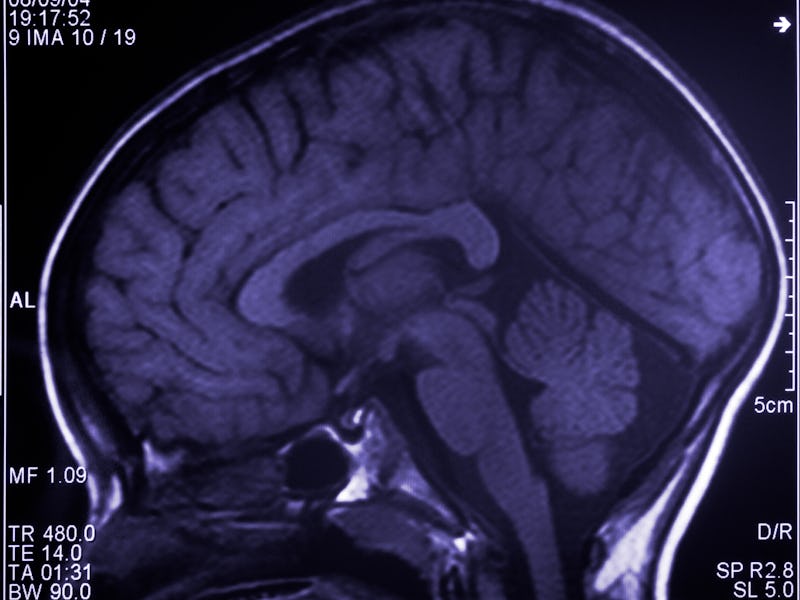

Recently, a pair of new studies about how binge drinking affects the brain discovered critical links between heavy drinking and cognitive-behavioral issues. Scientists say excessive alcohol can not only trigger anxiety; it can have lasting negative impacts on how our brains function.

Our first story looks at the troubling link between binge drinking and empathy. With a study suggesting heavy drinkers need to work harder to feel others’ pain, researchers hope that by identifying how the brain responds to pain stimuli that engage empathy, we can better understand the mechanisms that make people binge drink in the first place.

Our second story is about how excessive alcohol can disrupt brain signaling and, ultimately, spike anxiety. While experts say this finding could one day influence future treatment, for now, they suggest drinking in moderation to avoid these negative mental health effects.